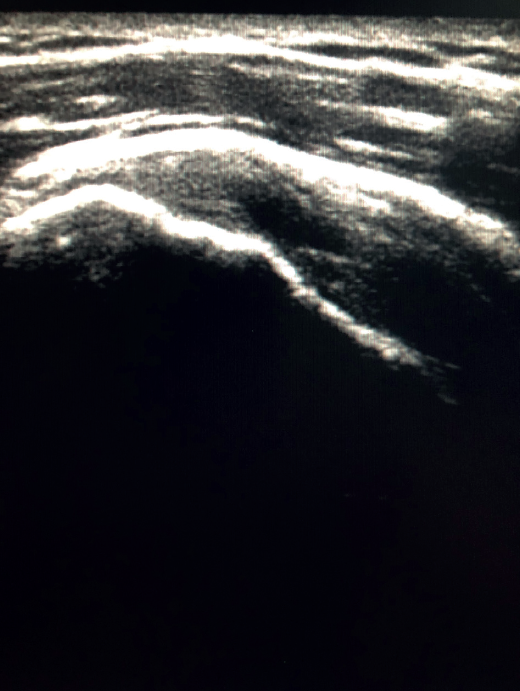

Figure 4. Anisotropy at the insertion of the tendon of the supraspinatus muscle. Not to be confused with partial thickness injury.

The characteristic ultrasound image of tendinosis consists of local or diffuse thickening accompanied by a hypoechogenic and heterogeneous appearance of the tendon (Figure 3). A fine hypoechoic line over 2 mm in thickness between the tendon of the supraspinatus and the subdeltoid adipose tissue corresponds to subacromial-subdeltoid bursitis, and the presence of fluid in the bursa is related to a high probability of partial or complete injury of the tendon of the supraspinatus muscle(26). In order to achieve greater diagnostic accuracy and distinguish between an inflammatory process and a normal small amount of fluid in the bursa, we should take into account that bursitis, tenosynovitis and tendinitis are characterized by the presence of hyperechoic zones with areas of enhanced flow in the Doppler ultrasound study. Both bursal and articular partial ruptures appear as a hypoechoic discontinuity in the tendon that does not vary on modifying the inclination of the ultrasound probe in either the long axis of the tendon nor its short axis(19). This latter aspect is important in order not to confuse partial lesions with anisotropic phenomena, which are a change in tissue behaviour according to the ultrasound angle of incidence(27)(Figure 4).